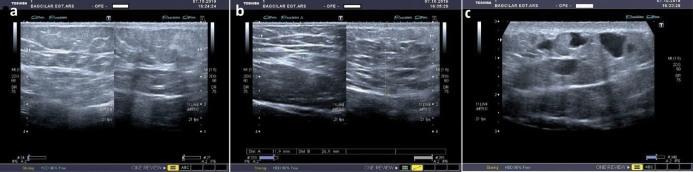

Unusual angiomatous or lymphangiomatous vascular malformations are rarely seen. One of them is lymphangioma (LA), which is a rare benign lymphovascular abnormality. LA is usually seen in the types of circumscriptum (or capillary), cavernous and cystic. Here, we report a unique case of LA with a patchy appearance. The patient presented due to unusual symptoms and eccentric clinical manifestation of the lesion. Here, we present a new lymphatic entity which was diagnosed as LA with its clinical, radiological and pathological findings. Written informed consent of the patient was obtained for this report. To the best of our knowledge this macular form of cutaneous LA has not been previously reported in literature. Macular LA should be kept in mind when faced with a colored long-term macular lesion on the skin.

罕见的血管瘤样或淋巴管瘤样血管畸形很少见。其中一种是淋巴管瘤(LA),它是一种罕见的良性淋巴血管异常。LA 通常见于局限性(或毛细血管)、海绵状和囊性。在此,我们报告了一个具有斑片状外观的 LA 独特病例。该患者因病变的异常症状和偏心临床表现就诊。在此,我们根据其临床、放射学和病理学表现提出了一种新的淋巴实体,诊断为 LA。本报告获得了患者的书面知情同意。据我们所知,这种皮肤 LA 的黄斑形式以前尚未在文献中报道过。当面对皮肤上长期存在的有色黄斑病变时,应考虑到黄斑状 LA。